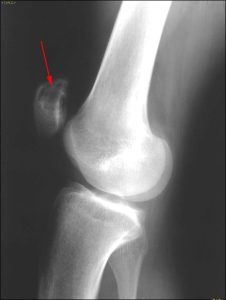

При осмотре и по жалобам выставить диагноз, и тем более степень хондромаляции, невозможно. Один характерный симптом указывает на наличие хондромаляции — это боль и дискомфорт при надавливании на надколенник, особенно при напряжении мышц и попытке сгибать ногу. Но этот симптом не является абсолютным, поэтому в диагностике этого заболевания предпочтение отдаются инструментальным методам. Рентгенограмма информативна на поздних стадиях, когда имеются признаки пателлофеморального артроза. МРТ и артроскопическая визуализация дают возможность установить диагноз на ранних стадиях, но артроскопия — это операция и она имеет свои ограничения.